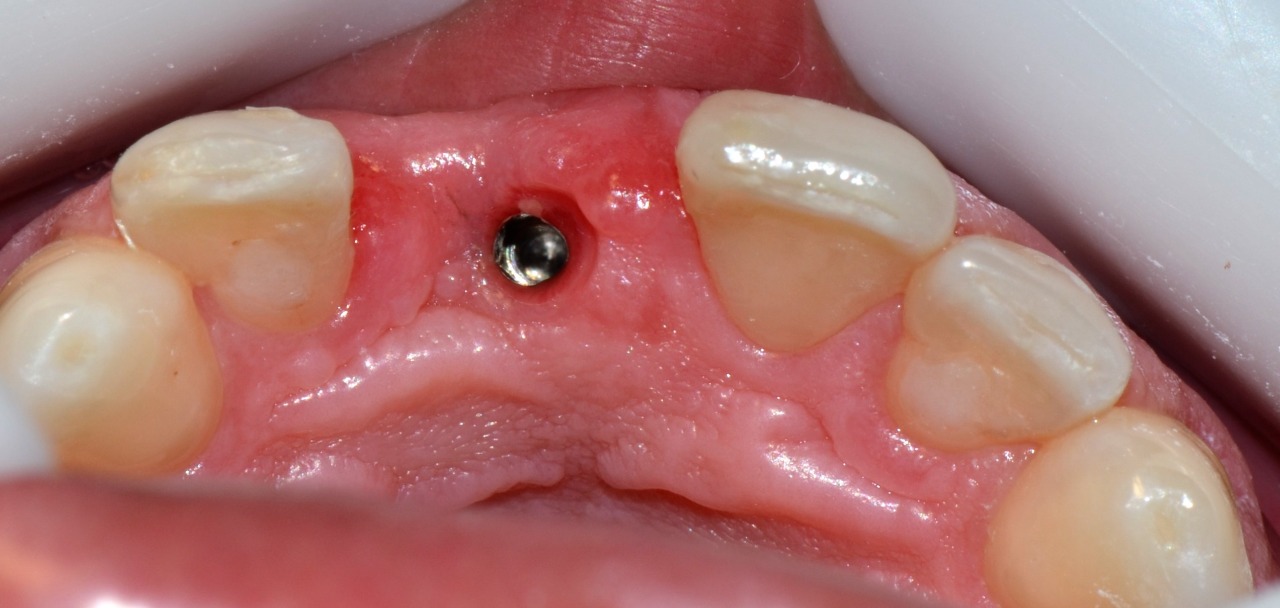

Depois da osseointegração do implante, foi realizada a reabertura e instalação de um cicatrizador. Em seguida foi feita a moldagem e confecção de uma prótese provisória em resina acrílica (em laboratório) para condicionar o tecido periimplantar da região e proporcionar a reabilitação protética definitiva. Foram realizadas restaurações em resina nos elementos 12 e 21 para condicionamento adequado das papilas interdentárias.